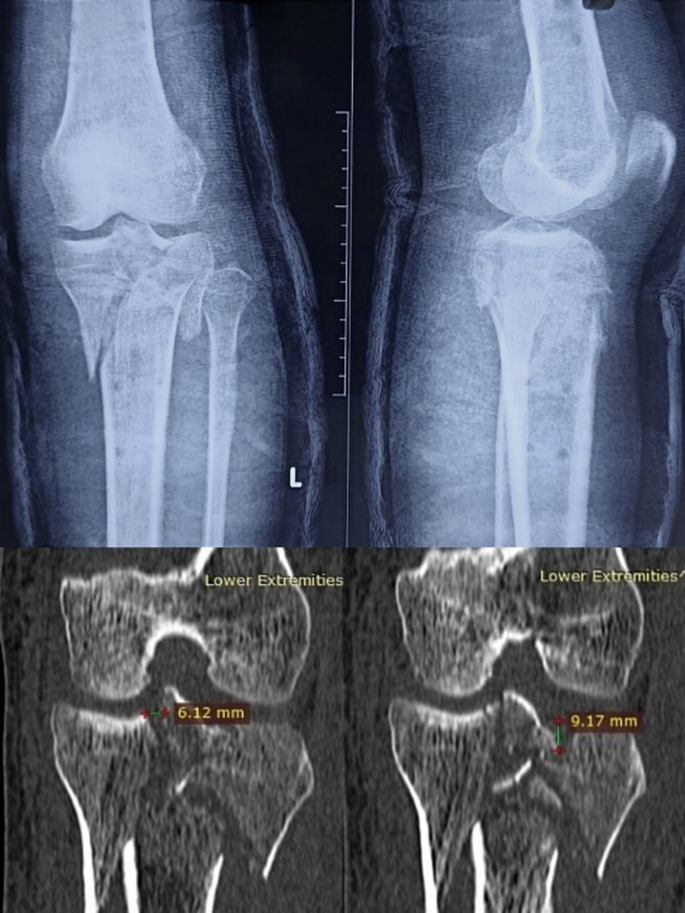

Case

A 32-year-old male patient involved in a traffic accident presented with a tibial plateau fracture as revealed by X-ray and CT scan (Fig. 5). The fracture was classified as Schatzker VI, and all three columns fracture. A 3D printing technique was employed to create a 1:1 solid prototype of the fracture. Surgeons performed in vitro simulation of the surgery using the model as guidance. During the actual operation, the model aided in achieving satisfactory fracture reduction and fixation, with the plate and screws positioned correctly. An 8-month follow-up X-ray demonstrated a well-aligned tibial plateau with visible callus formation. The Rasmussen score at this point was 23, indicating a good outcome, and the patient did not experience any surgical complications during this period (Fig. 6).

X-ray and CT scan images before the surgery.